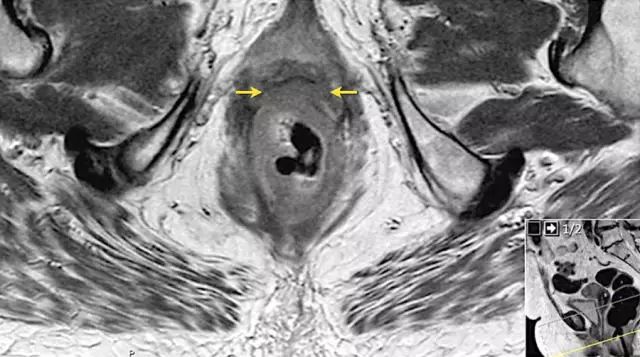

图 16 在矢状 T2W 图像上,直肠和阴道后壁之间有脂肪平面的损失。在轴向图像上,看到肿瘤的相对低的信号强度延伸到阴道的后壁(箭头)

以下 5 幅图例请连续观看:

图 17~21 肿瘤的低信号强度延伸到阴道的后壁(箭头)